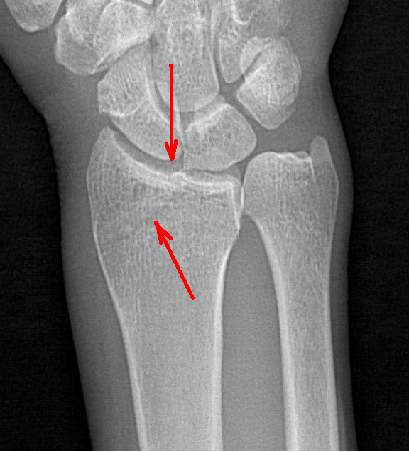

隱匿性骨折高清圖像

其次,動態(tài)DR 空間分辨率高,圖像清晰,診斷準(zhǔn)確率高,且具有視頻保存、回放功能,可以完整的記錄整個透視動態(tài)圖像,便于重復(fù)觀察、分析,減少遺漏。相對于傳統(tǒng) X 線檢查,動態(tài)DR輻射量較小,可有效減少 X 線所造成的輻射,呵護(hù)醫(yī)患健康。

普利德多功能動態(tài)DR將數(shù)字?jǐn)z影、數(shù)字透視、數(shù)字造影、毫秒級高清點(diǎn)片、影像實(shí)時保存與回放、全景拼接等多種功能集于一身。像素尺寸達(dá)到業(yè)界領(lǐng)先的100微米,率先實(shí)現(xiàn)5.0lp/mm超高分辨率成像,大幅提升細(xì)節(jié)檢測能力;透視幀率高達(dá)30幀/秒,有效避免漏診、誤診;靜態(tài)攝影有效像素高達(dá)1800萬,較之于傳統(tǒng)900萬點(diǎn)片像素,圖像細(xì)節(jié)更加清晰銳利,影像質(zhì)量躍升至新高度,為隱匿性肋骨骨折診斷提供至清影像,輔助醫(yī)生實(shí)現(xiàn)精準(zhǔn)診療!